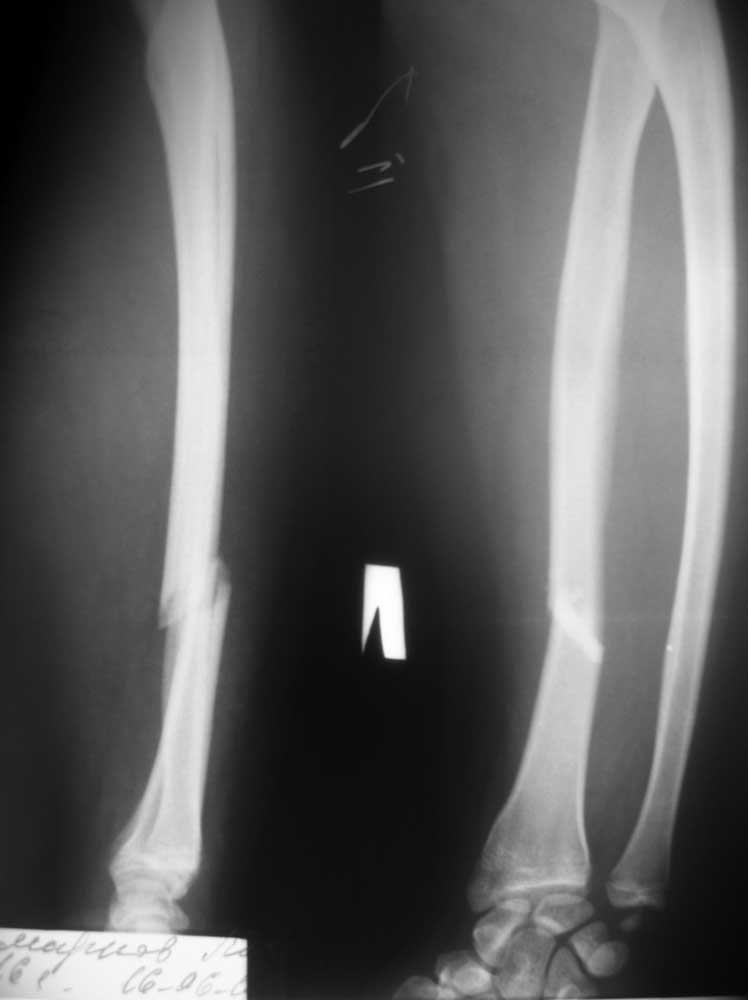

Перелом костей предплечья

Пострадавший, 16 лет, поступил в отделение 16.06.12. Травма в результате ДТП- воткнулся на скутере в неподвижный автомобиль. Других повреждений нет. За прошедшие выходные какими-то окольными путями умудрился получить консультацию сотрудника института травматологии и ортопедии, находящегося в областном центре. Сотрудник этот (д.м.н., профессор, весьма уважаемый в травматологическом, да и вообще во врачебном, сообществе нашего региона человек) рекомендовал консервативное лечение. Сам пострадавший, точнее, его родители, хотят отличного результата, отсутствие последствий, независимо от метода лечения, но находятся под влиянием слов профессора. Считаю, что такое повреждение просто необходимо оперировать, но чтобы переубедить пострадавшего, необходимо авторитетное мнение уважаемого сообщества.PS. Если операция, то может быть есть какие-то особенности. Заранее благодарен всем, высказавшим свое мнение. Любое!

Повреждения Галеацци с отрывом шиловидного отростка локтевой кости трудны для закрытой репозиции, склонны к вторичным смещениям. Разумеется,оперативное лечение обеспечит гарантированный результат.С диафизом понятно.Для радиоульнарного сочленения наверно проще позиционный винт.Желательно подшить и шиловидный отросток. Не понял,причём тут радиоульнарный угол?

Единственное показание к консервативному лечению - изолированный перелом локтевой кости почти или без смещения. Потеря формы и ротационных соотношений фрагментов лучевой кости приводят к функциональному дефициту, так что тут операция показана безусловно.

Классический перелом Галеацци с повреждением дистального лучелоктевого сочленения. Невозможно вправить вывих без восстановления длины луча.

Абсолютное показание к открытой репозиции луча со стабильной фиксацией (пластинка).

В большинстве случаев головка локтя вправляется сама и не требуется дополнительного вмешательства. Если в будущем возникают проблемы в лучезапястном суставе необходимо выполнить МРТ для выявления вида повреждения и решить о виде операции по восстановлению.